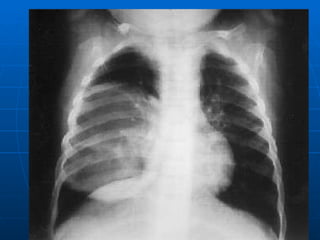

BRONQUIOLITIS:   Exámenes auxiliares Detección del VSR por inmunofuorescencia o por ELISA en secreciones respiratorias. Cultivos celulares es el patrón de oro. Oximetría y gases arteriales. Hemograma, VSG, PCR. Radiografía de tórax : Aunque se solicita en forma rutinaria no existe clara evidencia de su utilidad en la mayoría de pacientes. Puede ser normal  o presencia de hiperinsuflación, atelectasias y compromiso intersticial perihiliar bilateral. En 20% se reporta consolidación sin significar sobreinfección.

Bronquiolitis:  Estudio radiológico